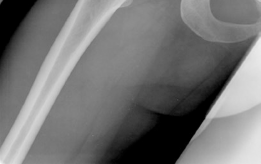

The radiographic evaluation of the dysplastic hip requires a highly standardized and rigorous protocol to accurately quantify the three-dimensional deformity. The initial assessment begins with a standing anteroposterior (AP) radiograph of the pelvis. In this patient, the AP view immediately reveals the hallmark signs of DDH: decreased anterolateral coverage of the femoral head and a broken Shenton line. The broken Shenton line—a step-off between the medial border of the femoral neck and the inferior border of the superior pubic ramus—indicates proximal and lateral migration of the femoral head due to structural instability. Furthermore, we observe an increased Tönnis angle (acetabular inclination) and a significantly reduced Lateral Center Edge Angle (LCEA) of Wiberg, confirming the diagnosis of severe lateral uncoverage.

The most critical functional radiograph in our preoperative workup is the AP Abduction view (often taken with the hip in 20-30 degrees of abduction and slight internal rotation). This view simulates the mechanical effect of a periacetabular osteotomy by effectively "rotating" the femoral head deeper into the acetabular dome. In this patient's case, the abduction view demonstrates excellent achievable congruency and congruity. The joint space becomes symmetric, and the femoral head centralizes perfectly within the socket. This is the ultimate litmus test for joint preservation: if the abduction view shows persistent incongruency or a "hinging" effect where the joint space narrows medially, a reorientation osteotomy may be contraindicated, as it would simply rotate a misshapen socket over a misshapen head, accelerating arthrosis.

To complete the diagnostic picture, advanced cross-sectional imaging is employed. A high-resolution Magnetic Resonance Imaging (MRI) arthrogram is the gold standard for evaluating the intra-articular soft tissues. In this patient, the MRI confirms a complex tear of the anterosuperior labrum, with associated paralabral cysts indicating chronic failure of the suction seal. Crucially, we utilize delayed gadolinium-enhanced MRI of cartilage (dGEMRIC) or T2 mapping to assess the biochemical integrity of the hyaline cartilage. The patient demonstrates preserved cartilage thickness without deep delamination or full-thickness chondral defects, confirming that she is in the pre-arthritic phase of the dysplastic cascade and is an ideal candidate for a joint-preserving Bernese Periacetabular Osteotomy.